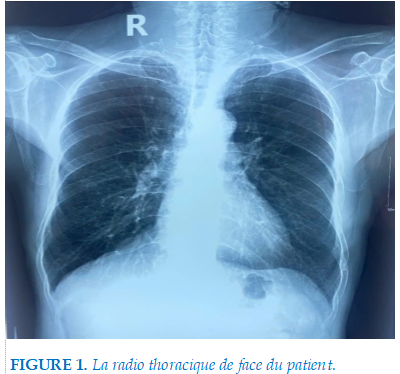

Le patient rapporte des épisodes de réveils nocturnes avec sensation d’étouffement, un ronflement ancien et intense, ainsi qu’une somnolence importante pendant la journée, confirmée par un score d’Epworth à 14/28. Le dépistage clinique par STOP-Bang a retrouvé 4 critères positifs, classant le patient dans la catégorie de risque élevé pour SAOS. Par ailleurs, l’examen physique ORL objectivait un Mallampati classe IV. Lors de l’hospitalisation, le patient a fait une radiographie thoracique qui ne montre pas d’anomalie majeure en dehors d’une dis tension thoracique: élargissement des espaces intercostaux et horizontalisation des côtes, et quelques plages d’emphysèmes (Figure 1). Les gaz du sang réalisées au même jour de la radio thoracique sous oxygène de 3L/min montrait la PaO2= 124 mmHg, la PaCO2=33 mmHg, le pH=7,42, l’HCO3-=22,4 mEq/L.